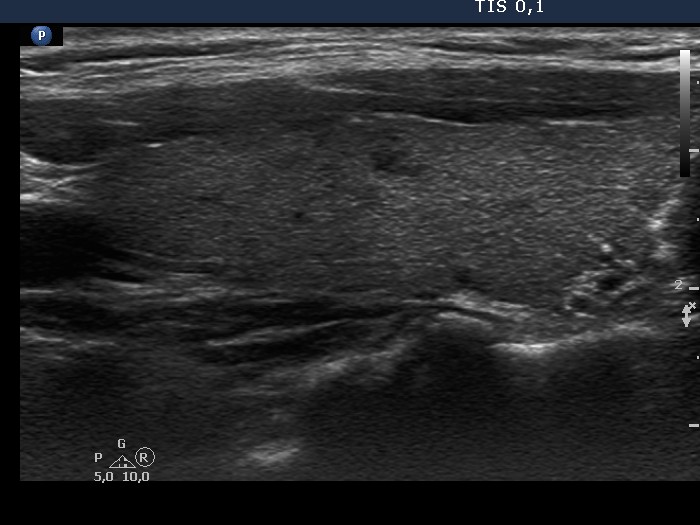

Consecutive patients with the final diagnosis of Hashimoto's thyroiditis - case 24 (10) (ultrasonographic picture 2)

Right lobe, longitudinal scan. The upper part of the lobe is minimally-moderately hypoechogenic while the lower part is almost echonormal but more, inhomogeneous.